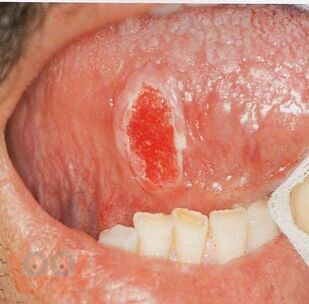

Le manuel présente des données modernes sur la tuberculose orofaciale. Les questions d'étiologie, de classification, de pathogenèse, de facteurs de risque, de clinique, de diagnostic, de diagnostic différentiel sont décrites en détail. Un algorithme d'examen des patients suspects de tuberculose orofaciale et les principes de son traitement sont présentés.

Compte tenu de la rareté du développement de la tuberculose de cette localisation, le matériel de manuel est illustré par les données cliniques des patients atteints de tuberculose orofaciale vérifiée, qui sont accessibles au public et publiées sur Internet dans des revues spécialisées.